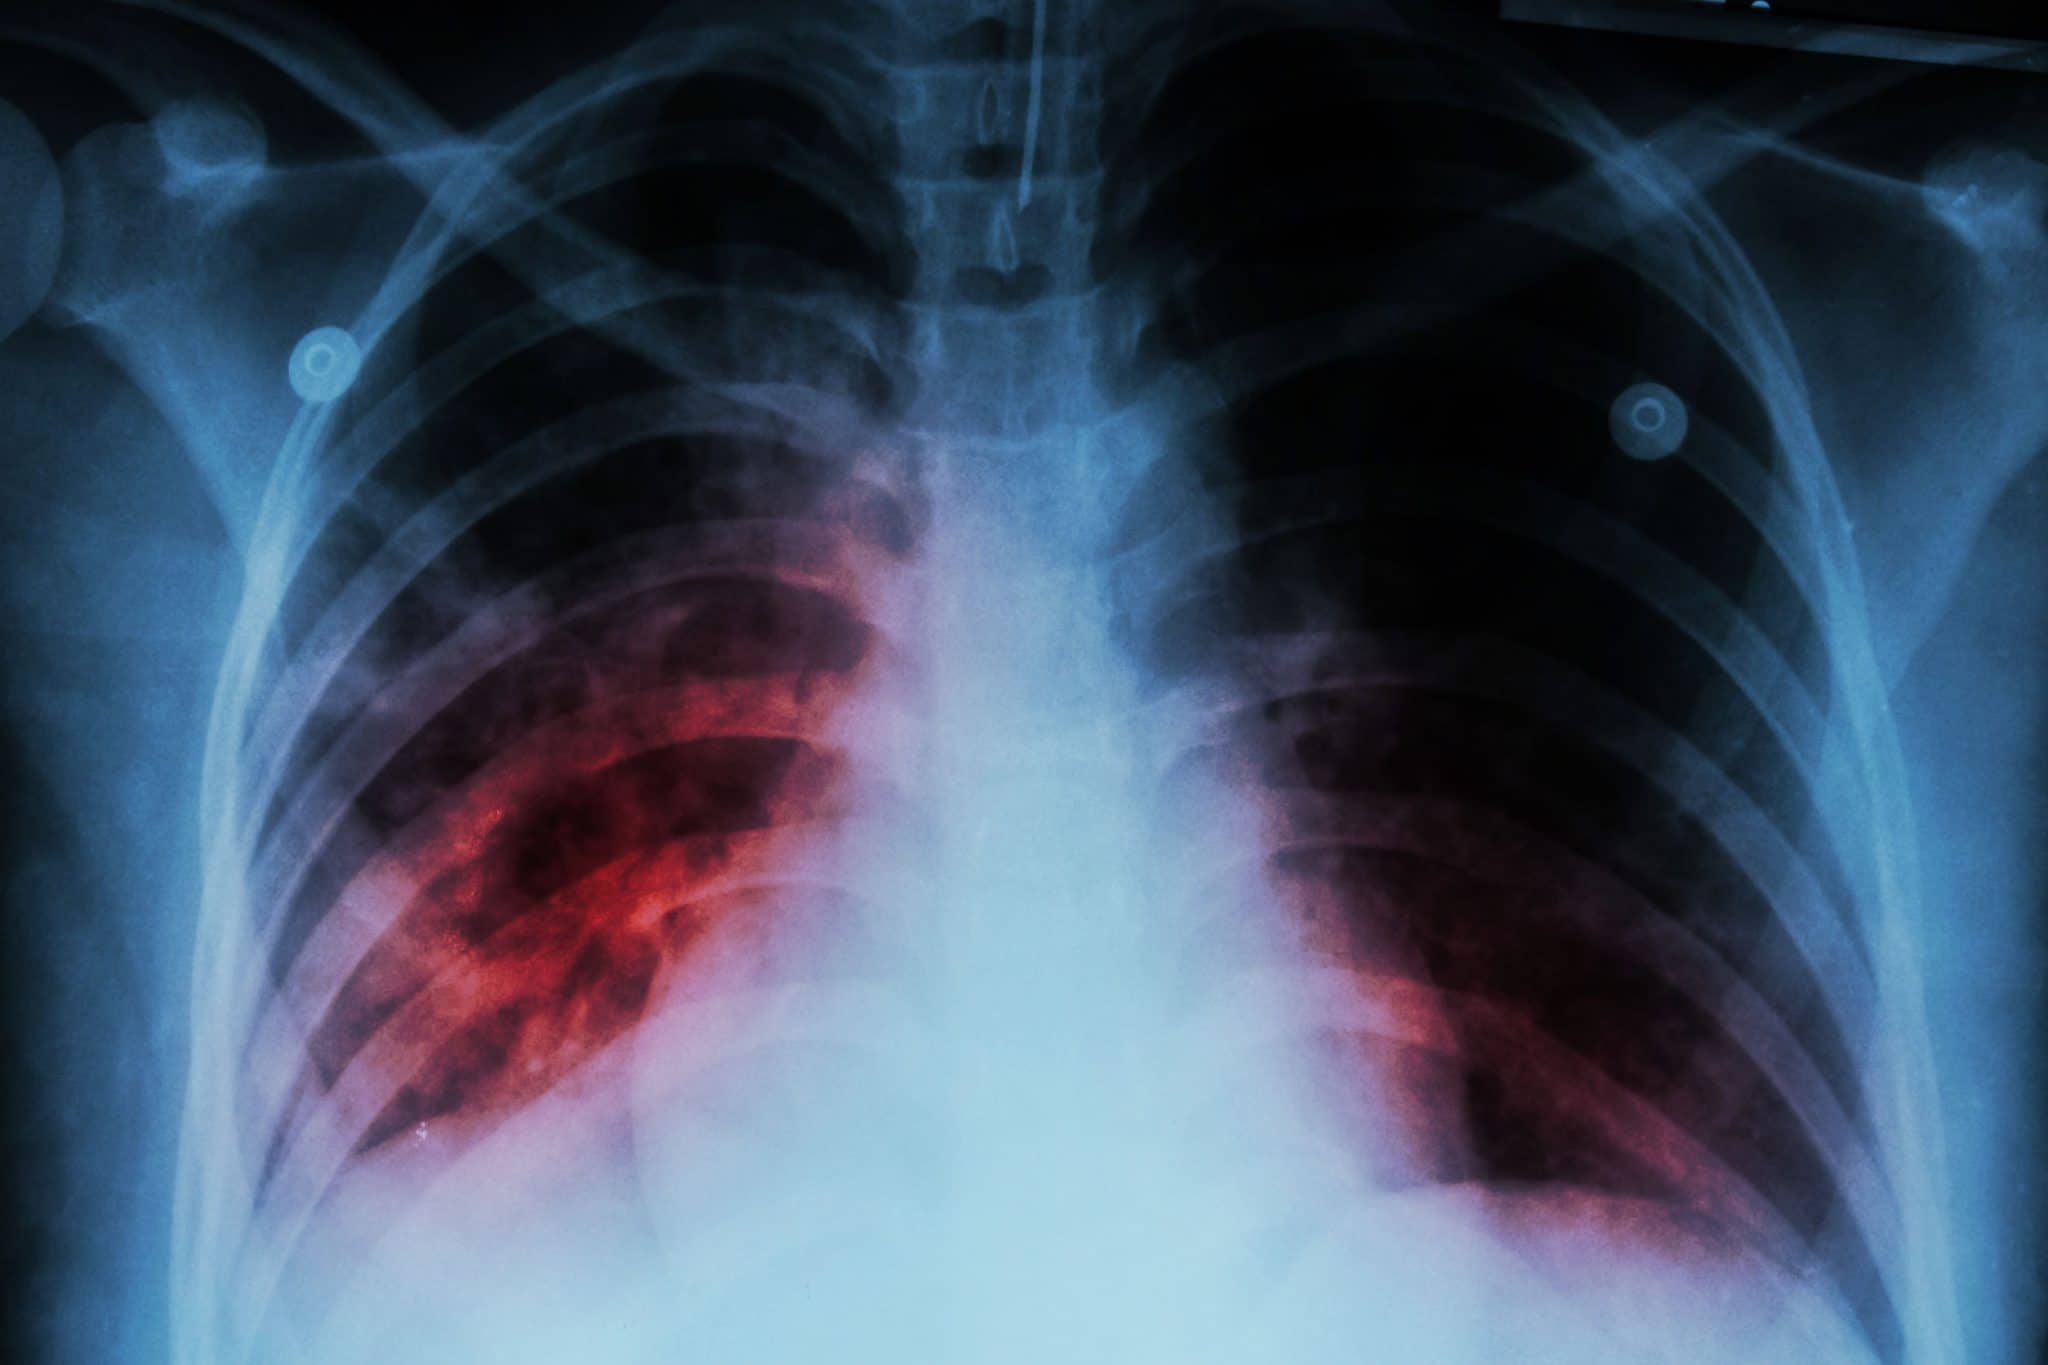

Tuberculosis (TB)